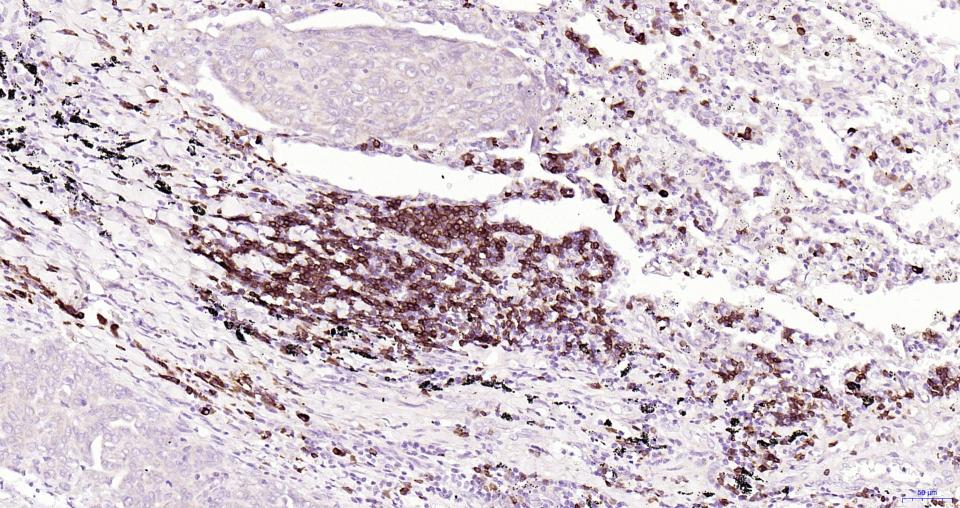

Paraformaldehyde-fixed, paraffin embedded Human Lymph; Antigen retrieval by boiling in sodium citrate buffer (pH6.0) for 15 min; Antibody incubation with CD79A Monoclonal Antibody, Unconjugated(bsm-60791R) at 1:200 overnight at 4°C, followed by conjugation to the SP Kit (Rabbit, SP-0023) and DAB (C-0010) staining.

Paraformaldehyde-fixed, paraffin embedded Human Appendix; Antigen retrieval by boiling in sodium citrate buffer (pH6.0) for 15 min; Antibody incubation with CD79A Monoclonal Antibody, Unconjugated(bsm-60791R) at 1:200 overnight at 4°C, followed by conjugation to the SP Kit (Rabbit, SP-0023) and DAB (C-0010) staining.

Paraformaldehyde-fixed, paraffin embedded Human Lung Cancer; Antigen retrieval by boiling in sodium citrate buffer (pH6.0) for 15 min; Antibody incubation with CD79A Monoclonal Antibody, Unconjugated(bsm-60791R) at 1:200 overnight at 4°C, followed by conjugation to the SP Kit (Rabbit, SP-0023) and DAB (C-0010) staining.